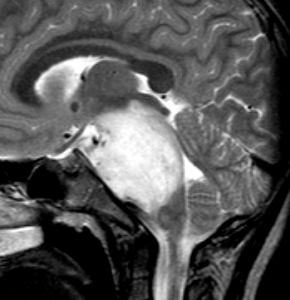

MRI画像診断

- MRIでは脳幹部(とくに橋)が腫れて大きくなります

- MRIのFLAIR(フレア)画像とかT2強調画像で,白くぼーっと滲んだように映ります

- 脳幹部の橋というところを中心にして発生し,上方の中脳や下方の延髄に浸潤して伸びていきます

- ガドリニウムという造影剤を静脈注射してMRIをとると一部分で白く増強されることが多いです

- ガドリニウムでリング状に増強される腫瘍は生存期間が短いとされています

- 腫瘍は大きいのですが,水頭症にならないのが特徴です(水頭症は2割くらい)

- 腫瘍の前方の中心に黒い点のようなものが見えますが,これは脳底動脈で,この脳底動脈の囲い込み engulfment は,DIPGに特徴的なものといえます